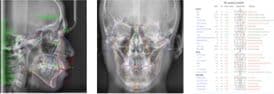

検査した内容を分析し患者様の今の状況(現在の上下顎骨のバランスやその骨に対しての歯の位置や上下の歯の位置や角度が標準値と比較した状況のチェック)からどこまで治療が可能かのシュミレーションを作成します。また、具体的な期間、装置、費用の説明などを行います。

検査データの解析

解析したデータから治療ゴールの制作